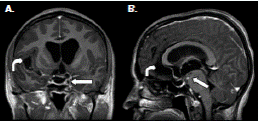

Figura 2 Resonancia magnética cerebral. A. Corte coronal potenciado en T1 con contraste; se observa hidrocefalia por dilatación ventricular asimétrica, realce basal y periquiasmático (flecha recta), y aumento del espacio subaracnoideo en el valle silviano derecho (flecha curva). B. Corte sagital, potenciado en T1 con contraste; se observa realce perimesencefálico por aracnoiditis (flecha recta) y aumento del espacio subaracnoideo en la lámina terminal (flecha curva).

Según los hallazgos en las imágenes de resonancia magnética cerebral, los casos informados se clasificaron como neurocisticercosis extraparenquimatosa con quistes racimosos en el espacio subaracnoideo asociados a la intensa reacción inflamatoria (figura 1), (figura 4).

En los dos casos que se presentan, la neurocisticercosis racemosa (sic) se acompañó de hidrocefalia y aracnoiditis; en el primer caso, además, se detectó vasculitis de la arteria cerebral media derecha en sus porciones proximales adyacentes a las cisternas de la base y la silviana derecha, relacionada con la presencia de cisticercos (figura 1). En el segundo caso, se detectó dilatación y obstrucción del cuarto ventrículo por aracnoiditis (figura 3), hallazgo que explica la causa del vómito incoercible, debido a su estrecha relación anatómica con el área postrema (control del vómito).